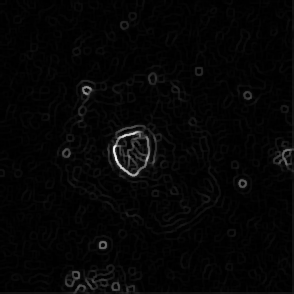

(a) Frame 1. Cell attachment phase

(b) Frame 2. Beginning of cell spreading

Figure 3: Original images of sequence is example of high dynamics of cell behavior affecting on contrast properties

The Fig.3 is representing couple of frames of sample image sequence with relatively high contrast between foreground and can be segmented with almost 95% accuracy with any method we used. Frame 1 of sample sequence presented at Fig.3(a) contain regions of hyper contrast pixels. In this case such condition does not affect on valid recognition since they are belong to object and present on margins of it and differs well from background. For Frame 2 there is absence of such pixels (Fig.3(b)) and this conditions also makes segmentation possible in relatively inflexible filtering conditions. The Frame 2 has relatively low contrast however it is seen that after filtration applied on image we achieve good difference of core and cell body compared to background as it presented at Fig.4 .